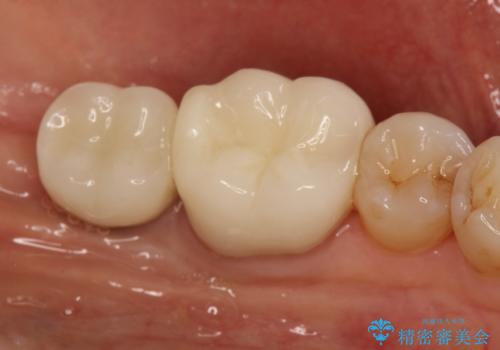

失った歯のインプラントでの咬合回復

- 左下の1番後方の歯が欠損しており、インプラントにて咬合回復する計画としました。